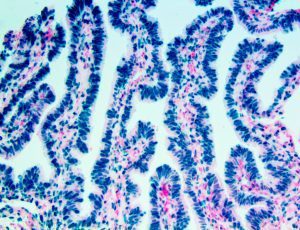

The first cytokines released are interleukin 1β (IL-1β) and tumor necrosis factor-α (TNF-α), which attract a variety of circulating white blood cells (WBCs) to the infection site, including neutrophils, monocytes, macrophages, and natural killer (NK) cells. This response, along with the antipathogenic chemicals released by these cells (i.e., complement), comprise the innate immune response. These cells directly attack the invading pathogen and also release additional cytokines, chief among them interleukin-1 and 6 (IL-6). IL-6 is essential for invoking the adaptive immune response, which calls T-cells, B-cells, and T helper (Th) cells to the infection site. IL-6 also stimulates further recruitment, proliferation and activation of macrophages.

It is the ICU physician who is most likely to witness one of the deadliest manifestations of the abnormal immunological response, the cytokine storm syndrome (CSS). This response is also referred to by some as the cytokine release syndrome (CRS). CSS is characterized by continuous activation and expansion of macrophage and lymphocyte populations, which secrete large amounts of cytokines, causing the cytokine storm. This massive cytokine release is akin to hemophagocytic lymphohistiocytosis (HLH) disease, a syndrome characterized by initial unchecked and persistent activation of cytotoxic T lymphocytes and NK cells.